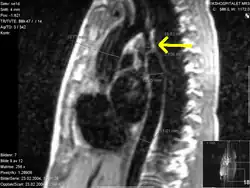

Koarktace aorty je vrozená vada představující zúžení aorty nejčastěji v oblasti Botallovy dučeje.

Kvůli zúžení aorty po odstupu tepen zásobujících hlavu a horní končetiny dochází u postiženého dítěte ke snížení tlaku a zhoršenému prokrvení břišních orgánů a dolních končetin, naopak horní polovina těla je zásobena pod vysokým krevním tlakem. Koarktace aorty je tedy hlavním důvodem tzv. kardiálního původu sekundární hypertenze.